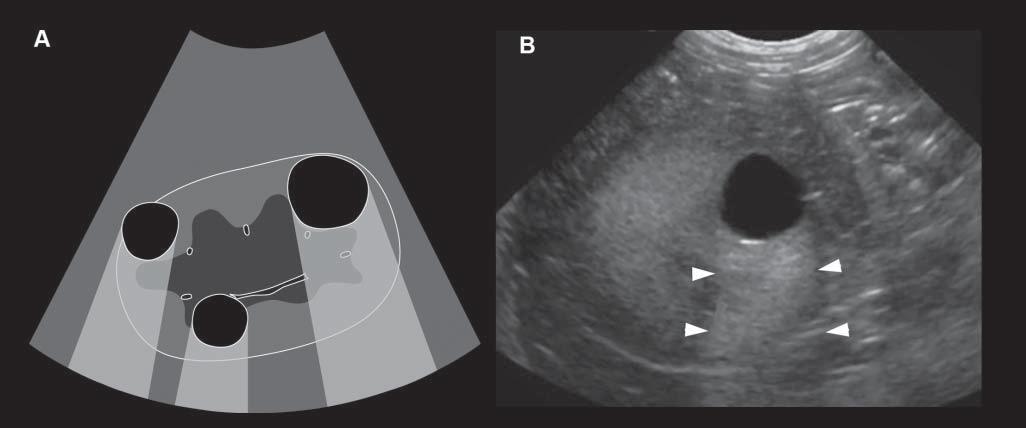

Spatialcompoundimaging (whichvariesinname amongbrands)referstotheelectronicsteeringof ultrasoundbeamsfromanarraytransducertoimage thesametissuemultipletimesbyusingparallelbeams orientedalongdifferentdirections(Hangiandreou etal.2003)(Figure1.9).Tissuesarescannedfrom differentangles,simultaneously,allowingmultiple echoesfromthesametissueinterfacestobecollected andcombined,increasingtheoverallsignaland

Figure1.9. Spatialcompoundimaging.A: Withthismode,thesametissueisscannedusingdifferentbeamangulations (steering)toproduceatrapezoidalimagethatiswiderthanthefootprintofthetransducer. B,C: Superficialstructuressuchas thiskidneymayexceedthesizeoftheimagefieldwhenthestandardlinearmode (B) isused,whereasspatialcompounding expandsthewidthoftheimagetoincludethekidney,whichcanbefullyassessedandmeasured (C).Beamangulationalso influencestheshapeandorientationofshadowingartifacts(arrowheads). reducingnoise.Imagecontrastisincreasedandtissue interfacesbecomemoreconspicuous.Tissuesboundariesarebetteroutlinedand,becausebackground noiseisreduced,cysticlesionsarefullyanechoicand thusmoreeasilydifferentiatedfromsolidlesions.On theotherhand,certainusefulartifacts,suchasacoustic shadowing–whichhelpsinrecognizingmineral,for instance–maydisappearwhencompoundimaging isused.Becausemultipleultrasoundbeamsareused tointerrogatethesametissueregion,moretimeis requiredfordatacollection,reducingtheframerate whencomparedwiththatofconventionalB-mode imaging.Thismodemaylimittheexaminationof movingpatients.